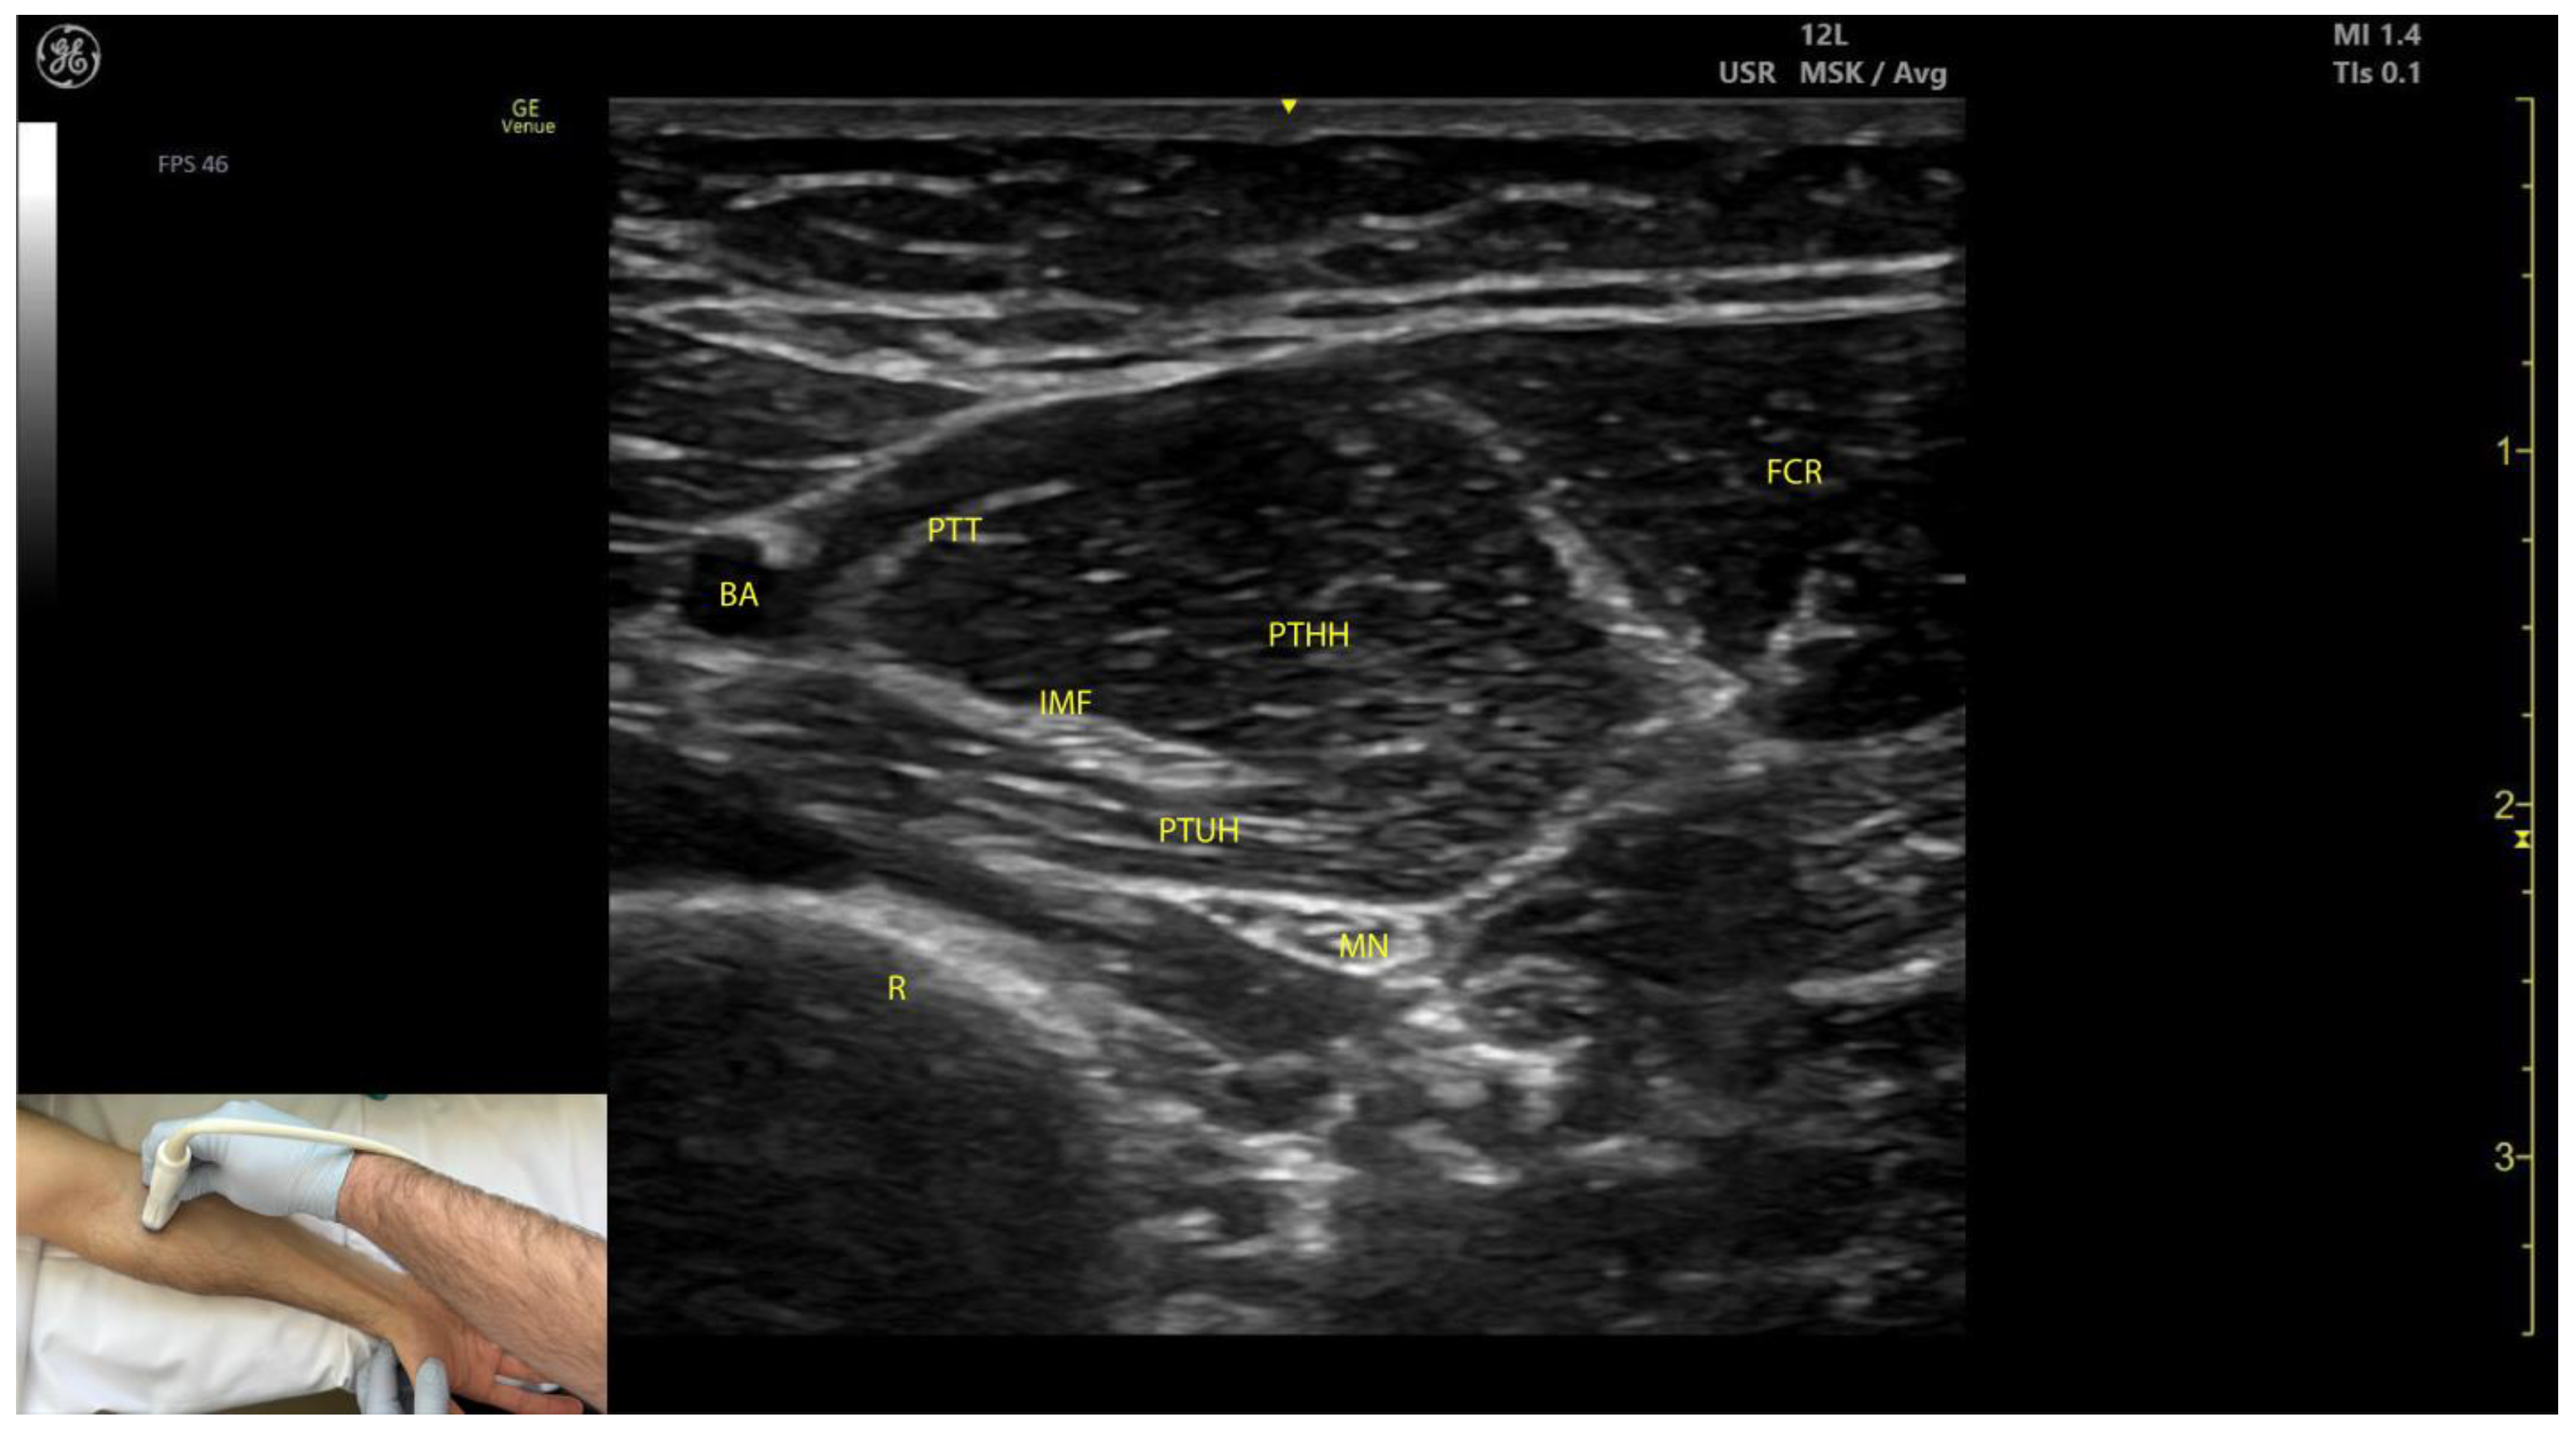

2.1.3. Key Ultrasound Landmarks (Figure 1)

- Muscle position: The PT is the first muscle mass from radial to ulnar on the volar aspect of the forearm [9].

- Intramuscular tendon: In the lateral portion of the muscle, it is positioned longitudinally along the muscle at this level.

- Internal fascia: The fascia separates the humeral (PTHH) and ulnar heads (PTUH) of the PT, while the external fascia distinctly demarcates the PT from adjacent muscle masses, facilitating precise BoNT-A injection.

- Median nerve: The nerve is located deep to the PT, approximately 2 cm distal to the elbow crease. Dynamic evaluation cranially towards the arm reveals the nerve transitioning to the lateral aspect of the muscle alongside the brachial artery [10].

- Dynamic evaluation (Video S1): Scanning proximally toward the medial epicondyle shows an increase in the PT muscle belly size and a concurrent decrease in the size of the FCR. At this level, the intramuscular fascia specific to the PT becomes evident, separating the two muscle heads—the humeral head and the ulnar head—allowing for individual targeting [11].